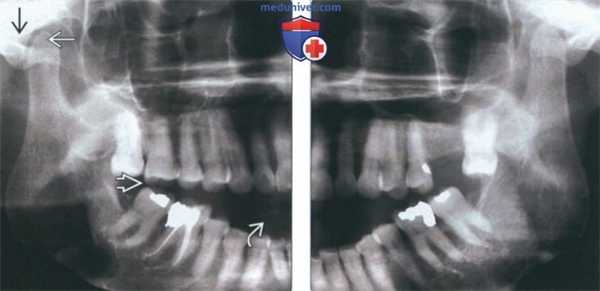

(Слева) На панорамной рентгенограмме у пациента с двухлоронним передним вывихом визуализируется правый мыщелок, смещенный кпереди и кверху относительно сулавного возвышения. Обратите внимание на явный передний открытый прикус, в то время как моляры находятся в окклюзии.

(Справа) На панорамной рентгенограмме у этого же пациента определяются аналогичные изменения слева. Открытый прикус обусловлен неправильным передним положением мыщелка, контакт задних зубов - его верхним положением.

2. Рентгенография при вывихе височно-нижнечелюстного сустава (ВНЧС):

• Радиографические признаки:

о Передне-верхнее положение мыщелков по отношению к суставному возвышению